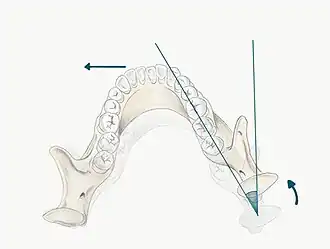

The patient may be guided into CR using one of the follow methods;

- Bimanual manipulation- manipulating the patient's condyles so they are in CR

- The operator should lightly rest their fingers along the inferior border of the mandible and their thumbs should lie lightly on the anterior aspect of the chin

- When the patient is relaxed place light downward pressure on the chin and light upward pressure under the angle of the mandible

- Deprogramme the jaw by guiding the opening and closing of the jaw and once the patient is relaxed, ask them to close gently and stop when they feel teeth first contacting

- Chin point guidance- one hand is used to apply pressure to the chin guiding the chin posteriorly with some force

In some patients it may be difficult to guide the mandible into CR, for example in those with muscle tension, muscle splinting, occlusal disharmony or parafunctional habit. For these patients a Lucia Jig or deprogramming appliance can be constructed at chair-side.

Mark RCP tooth contacts using articulating paper, note the teeth which are contacting and identify whether this RCP position is causing problems related to the occlusion. For example if there is a heavy contact or interference in RCP this may be the cause of occlusal disturbance. It is important to be able to guide the patient into RCP, as a registration may need to be taken in this position particularly if the occlusion is being reorganised, the OVD is being changed or even just for diagnostic and treatment planning purposes.